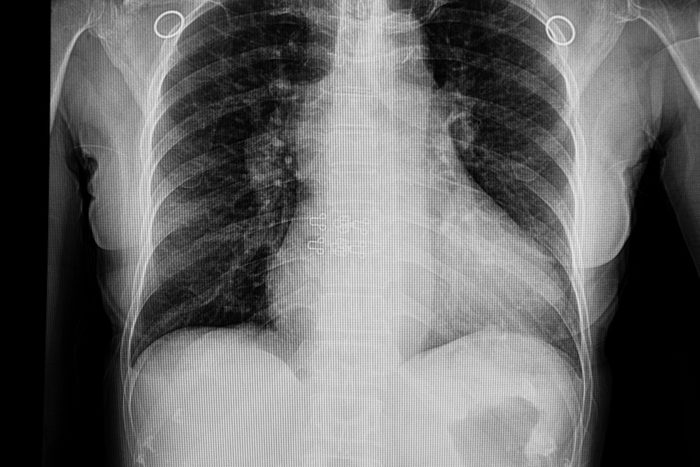

You may have pneumonia

What It Is: “Pneumonia is usually a wet cough with lots of mucus, and may cause breathlessness,” says Dr. Taliercio, and also may begin as an upper respiratory infection. Watch for these warning signs your upper respiratory infection is pneumonia.

What Causes It: Pneumonia is caused by an infection in the lungs that leads to the buildup of fluids in the chest, reports the Mayo Clinic.

Treatment: Your doctor can diagnose pneumonia with a chest x-ray. Bacterial pneumonia is usually treated with antibiotics, and in severe cases may require intravenous antibiotics,” says Dr. Taliercio.